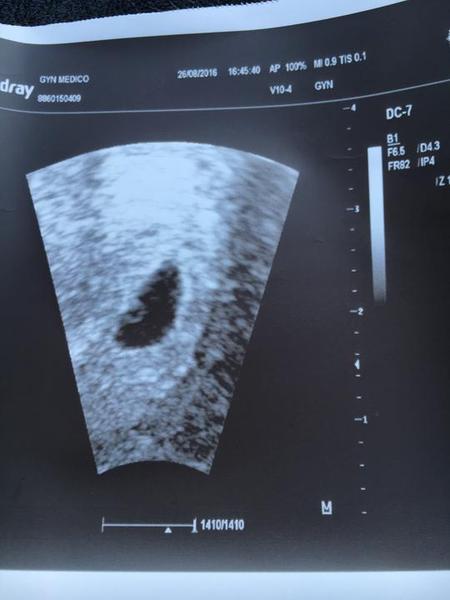

Ahoj holky.Kdyz jsem byla na utz v 5+5tt tak byla videt jen pidi midi tecka.na ko jdu pristi tyden.mate nektera foto utz z 5+5 a 4+5 na porovnani?